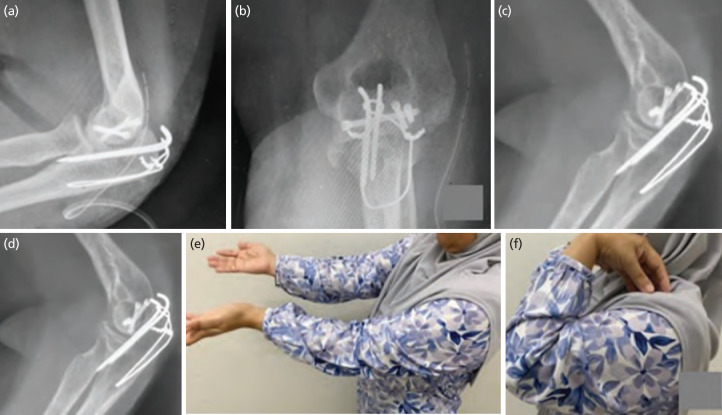

Articular fracture of distal humerus account for 2% of all adult elbow fracture. The coronal shear fracture combined with olecranon fracture require stable anatomical reduction and stabilisation for early rehabilitation and mobility. Numerous reports have described various approaches in tackling this type of fracture and method of fracture fixation. Here, we shared a case of a lady with traumatic coronal shear capitulum and trochlear comminuted fracture fixed using posterior elbow approach with fracture site open window technique in managing distal humerus articular fracture with ipsilateral olecranon fracture using headless screw and tension band wire. During last follow-up, fracture was united radiographically with congruent articular joint, patient able to return to her original function without limitation and no indications of avascular necrosis.